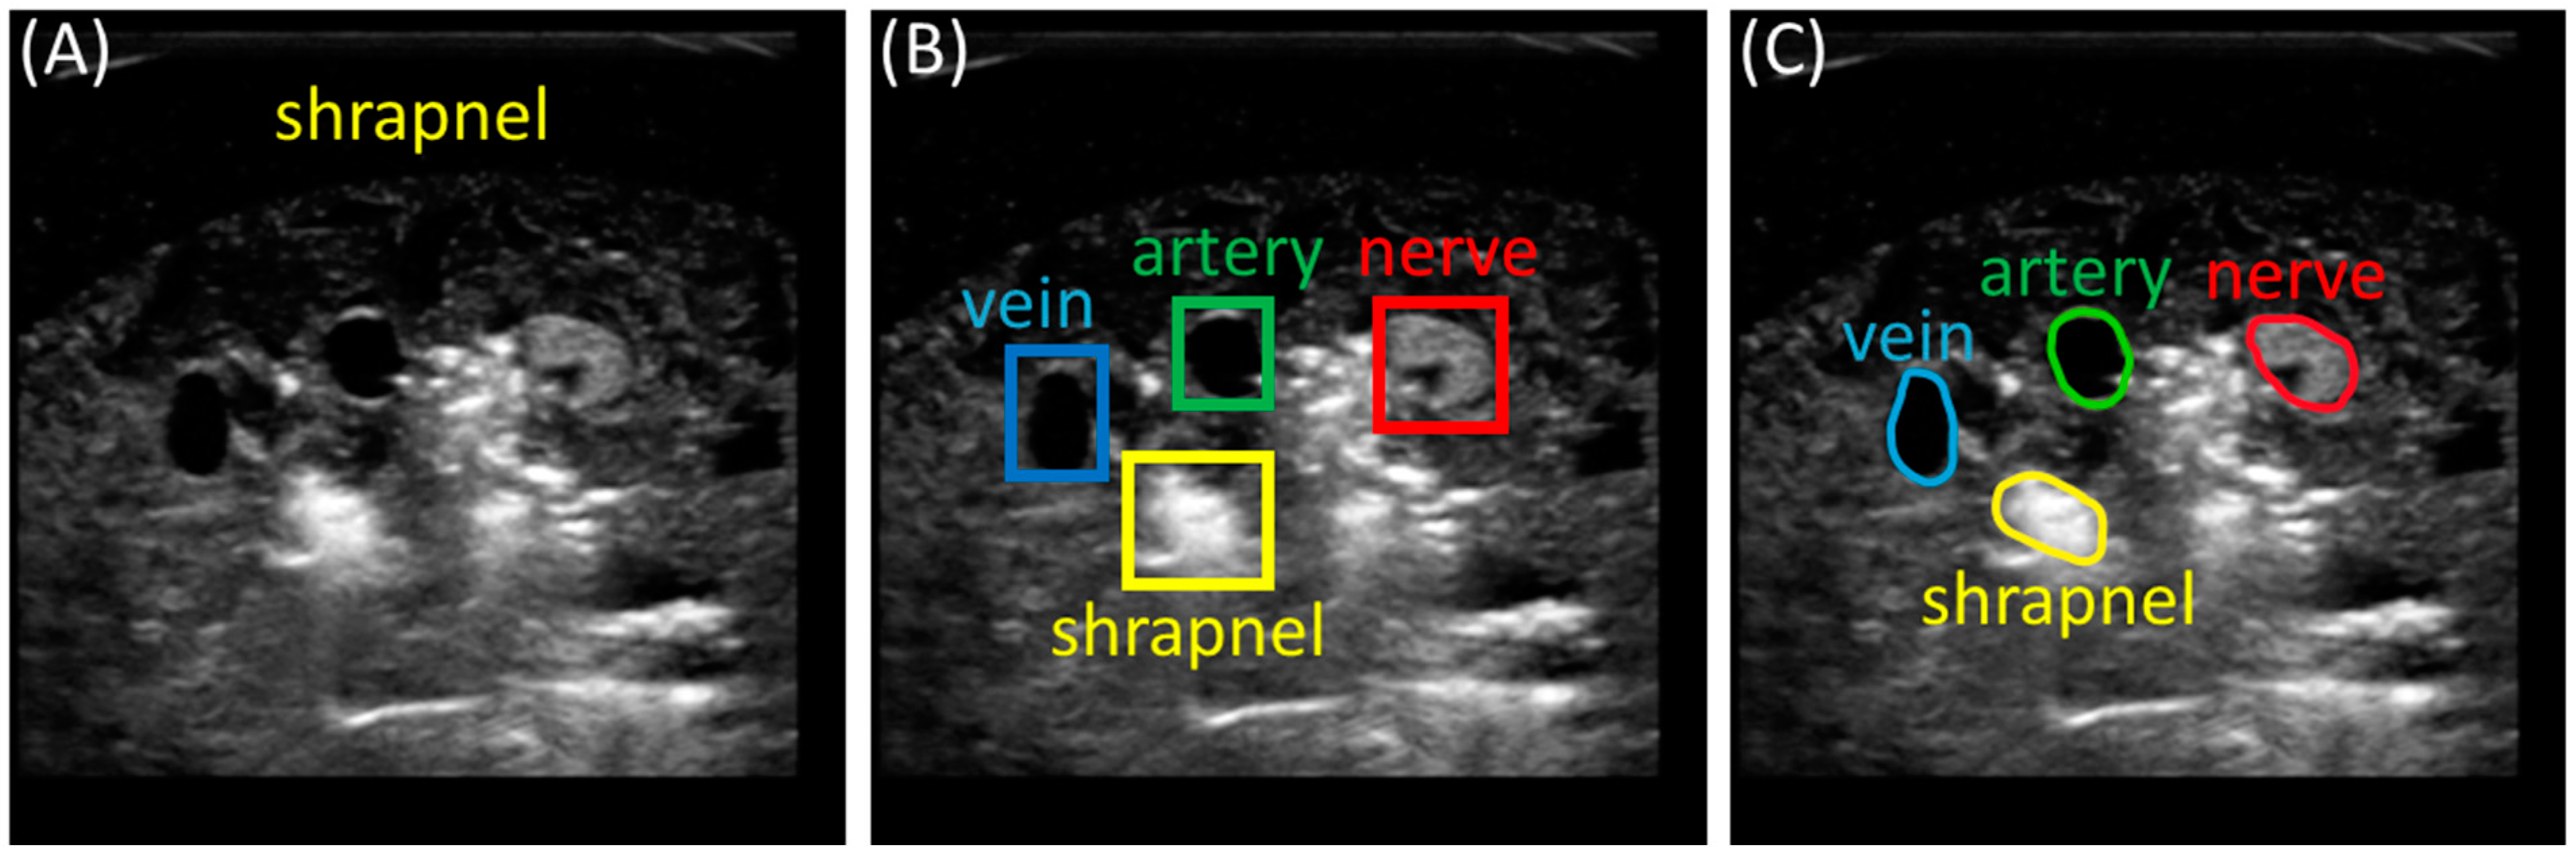

2.2. Preprocessing and Labeling Images

3.2. Multi-Class Segmentation Models